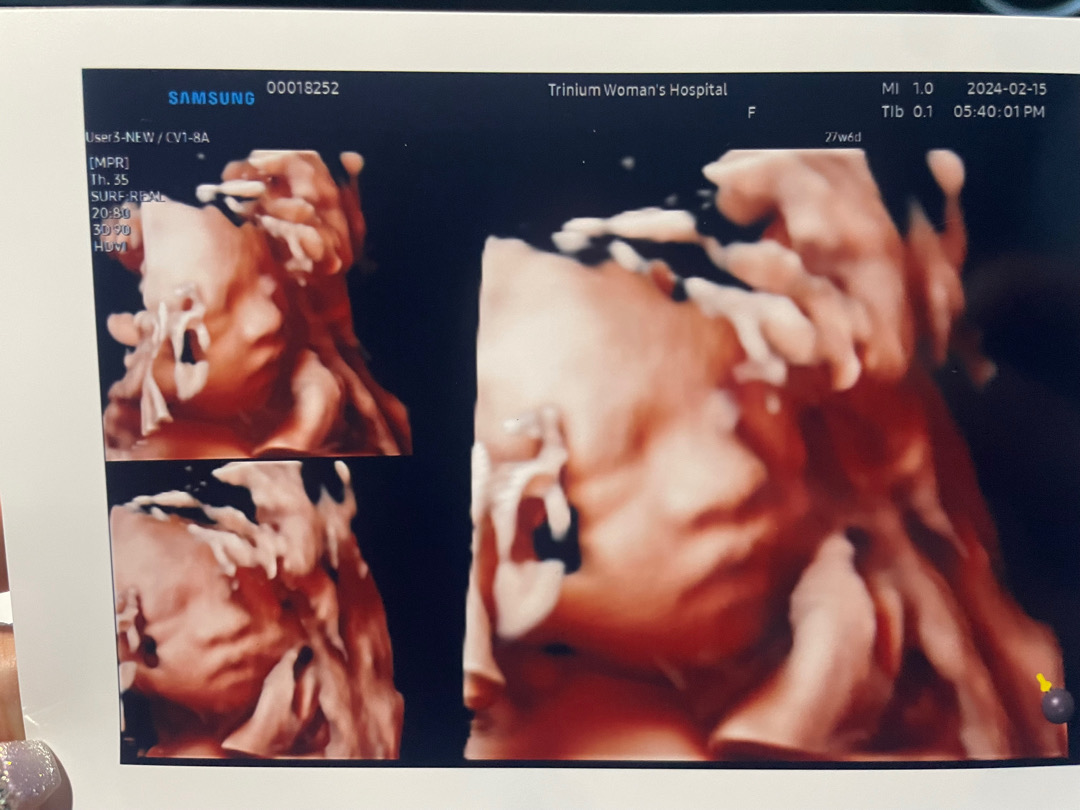

27주6일 입체초음파 봤어용

너무너무 귀여워서 빨리만나고싶어요🥹❤️